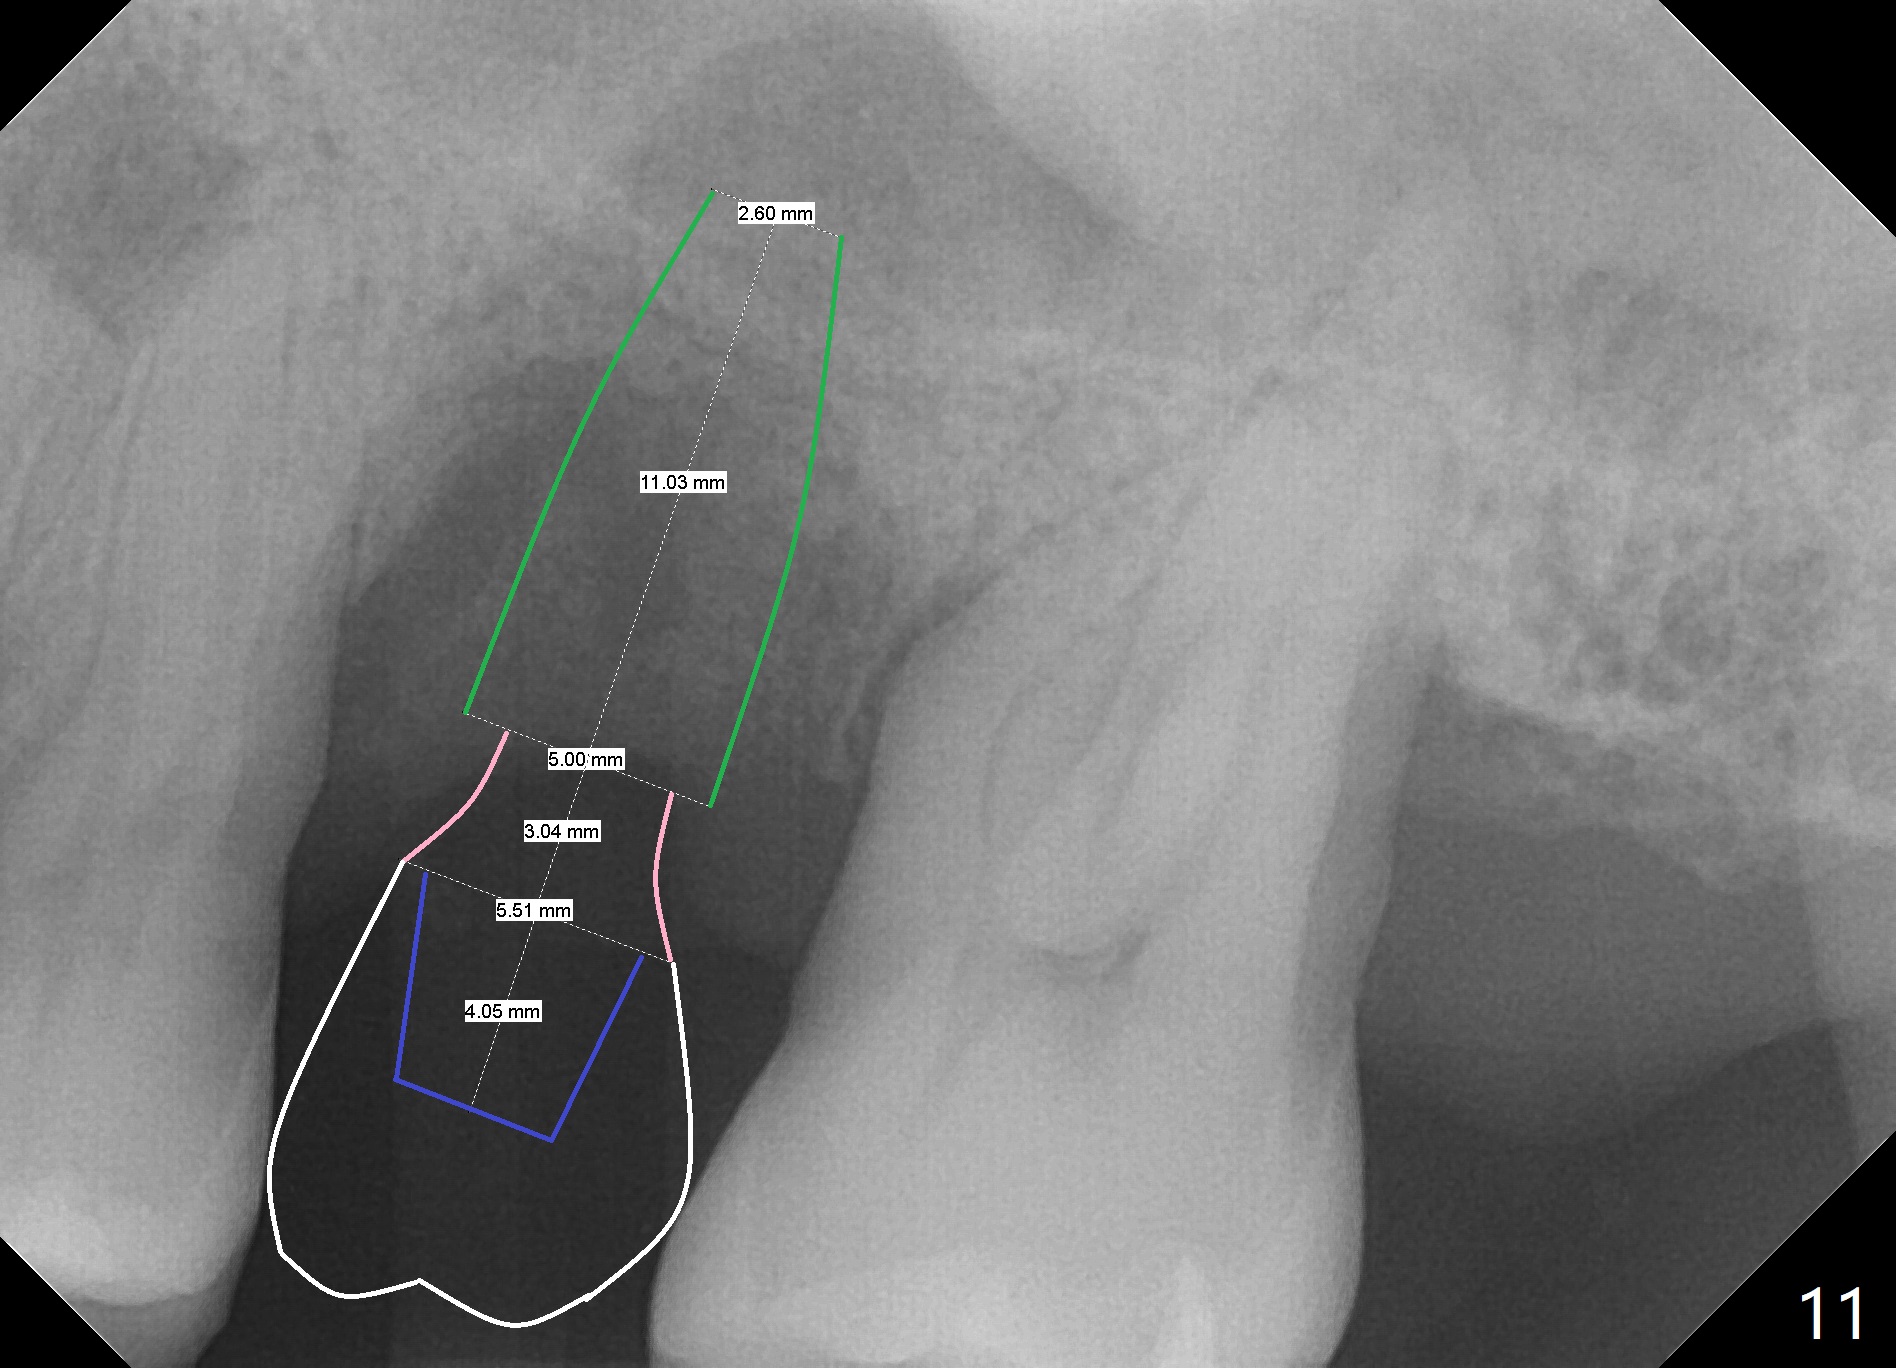

When the tooth #14 is extracted, the buccal plate is lost, while the apex of the palatal socket is perforated.  The palatal slope of the septum appears to be a suitable site for osteotomy, but the depth seems to be 2 mm.  After sequential osteotomy until 5.3 mm with drills, a 5.9 mm SM tap obtains stability (Fig.2).  A 5.9x8 mmm implant is placed with barely sufficient stability after 1 piece of PRF membrane and VeraGraft (Fig.2-4).  The implant rotates and dislodges when an abutment is being placed.  Neither do 6-8x17 mm Tatum taps achieve primary stability.  Socket preservation is performed, followed by periodontal dressing (Fig.5).  Primary stability might have been obtained if a smaller IBS implant with fins were placed in the palatal socket.  The periodontal dressing has dislodged 1 week postop; the socket appears healing (Fig.6,7).  Bone graft seems to be minimal or bone density of the graft is low (Fig.8).  The socket heals with a wide ridge 2 months post socket preservation, but the tooth #15 seems to be buccal (Fig.9) and mesial (Fig.10) shift.  After use of Magic Split and Expanders (until 3.8 mm for 13 mm), try 5 mm dummy implant (Fig.11).  If 6 mm one fails to achieve stability substantially, switch to 7 mm Tatum tapered tap provided there is enough mesiodistal space (use 8 mm implant positioner to gauze the space beforehand (preop)).  Consider using Vanilla (not Vera) Graft to fill in the gap between implant and osteotomy.  When primary stability is obtained, place a nonfunctional provisional to prevent further shifting (Fig.11 white outline).  After osteointegration, use the provisional (reline and separator) to distalize the tooth #15.